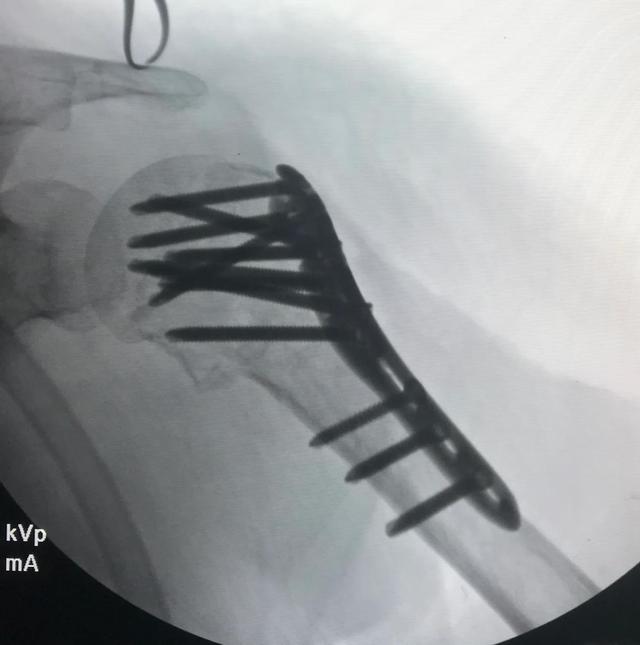

钢板内固定治疗

肱骨近端锁定钢板(LPHP)治疗缺点为存在广泛的手术暴露,会导致骨折周围软组织损伤,进而破坏血运,导致骨折无法愈合,增加肱骨头缺血坏死。优点是骨折固定稳定性较好,钢板为根据患者肱骨近端解剖形状加以设计的角稳定性钢板,可以肱骨近端牢固固定,骨质疏松性骨折可以获得显著效果。